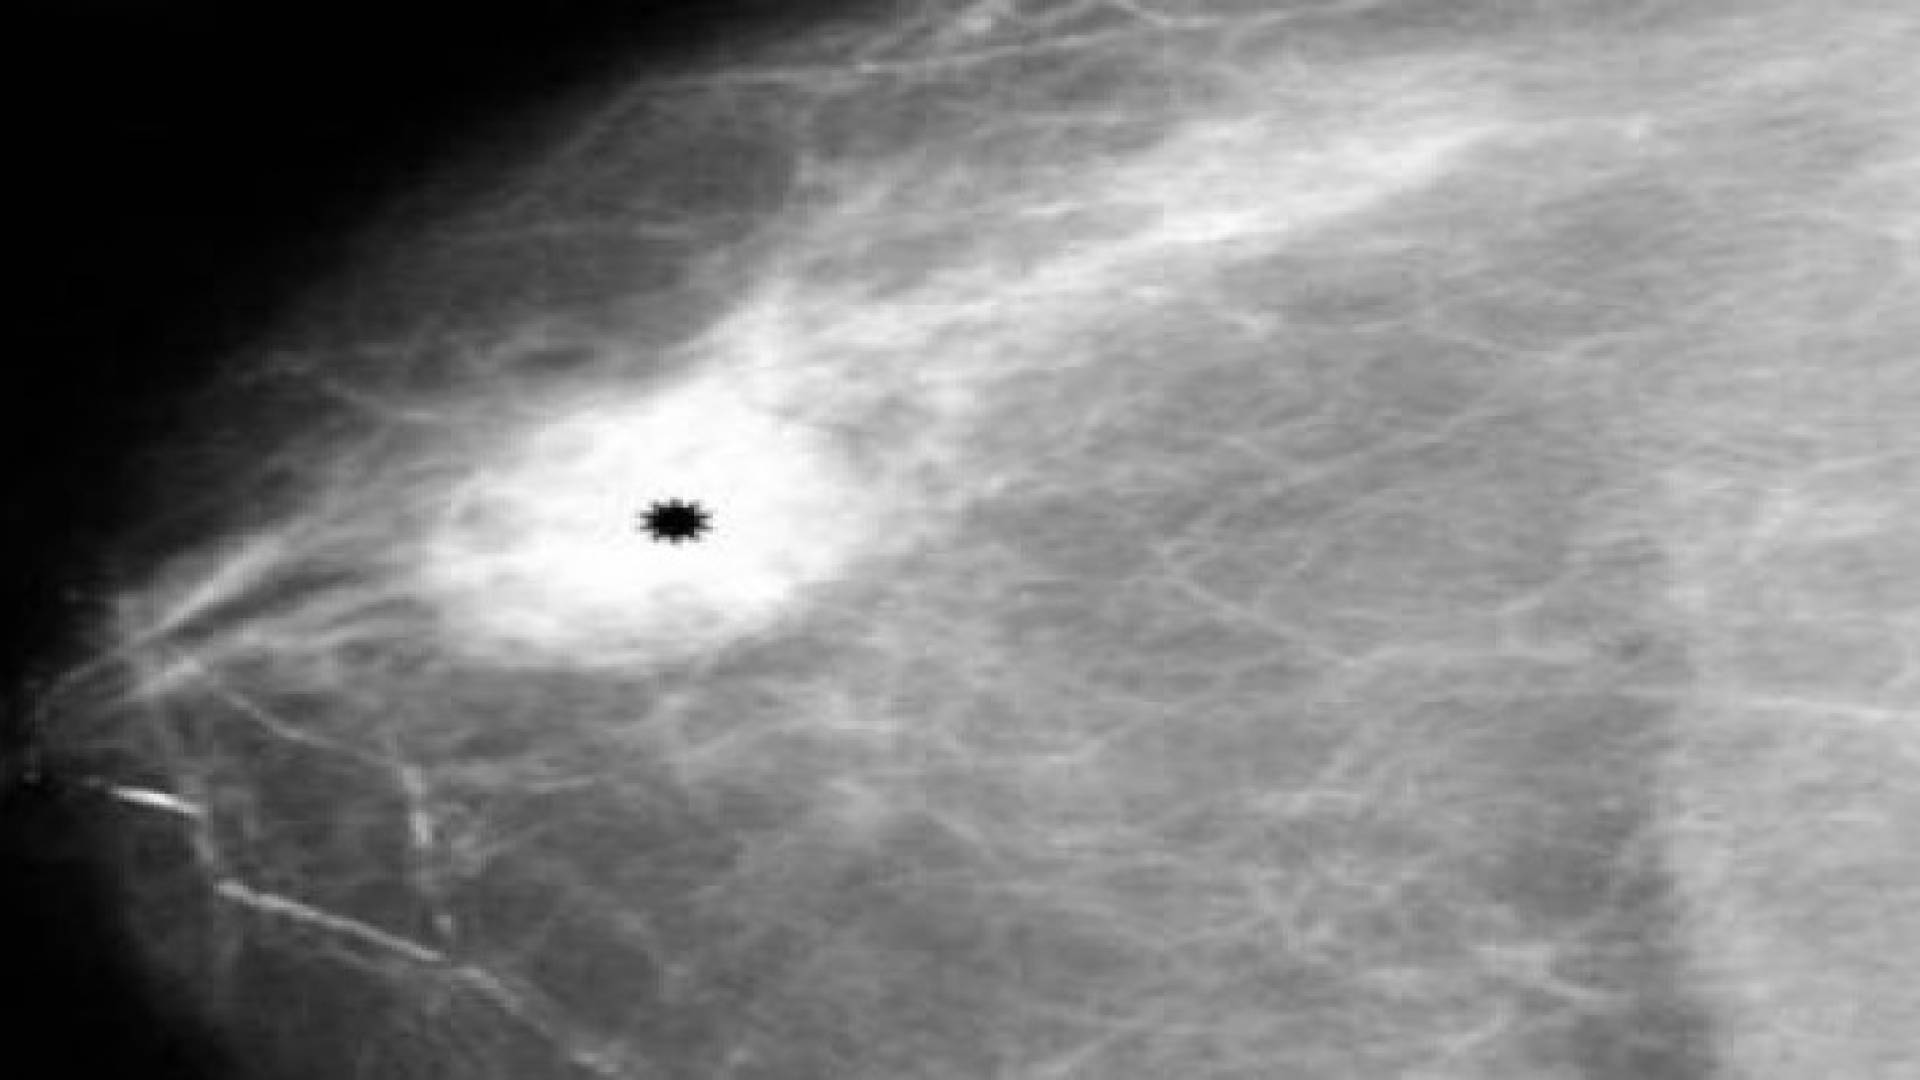

دواء رخيص يحسن علاج سرطان الثدي

رؤيا - ديلي تلغراف - أفادت دراسة جديدة بأن نصف مرضى سرطان الثدي يمكن أن يستفيدوا من إضافة هرمون البروجسترون الأنثوي إلى علاجهم.

فقد اكتشف العلماء أن هذا الهرمون يمكن أن يوقف نمو الورم. وتظهر الدراسة الجديدة التي نشرتها صحيفة ديلي تلغراف البريطانية كيفية تخاطب مستقبلات هرمون البروجسترون مع المستقبلات الأخرى الحساسة للبروجسترون، التي تزيد سرطان الثدي في عدد كبير من الحالات، وهذا الأمر له تأثير استخدام المكابح على قدرة مستقبلات البروجسترون لتحفيز الأورام.

ويشير الأطباء إلى أهمية هذه الدراسة في تحقيق الفائدة المحتملة من إضافة البروجسترون إلى العقاقير - الرخيصة والمتوفرة - التي تستهدف مستقبلات البروجسترون، التي يمكن أن تحسن علاج معظم حالات سرطان الثدي التي يحركها الهرمون.

يشار إلى أن نحو 50 ألف حالة جديدة لسرطان الثدي تشخص في بريطانيا كل عام، ويعتقد الباحثون أن نحو النصف يمكن أن يستفيدوا من هذا الاكتشاف.

وهذا يعني إمكانية وقف المرض من الانتشار في بقية أجزاء الجسم، وهو ما يزيد الآمال في علاج جديد للمرض منقذ للحياة.